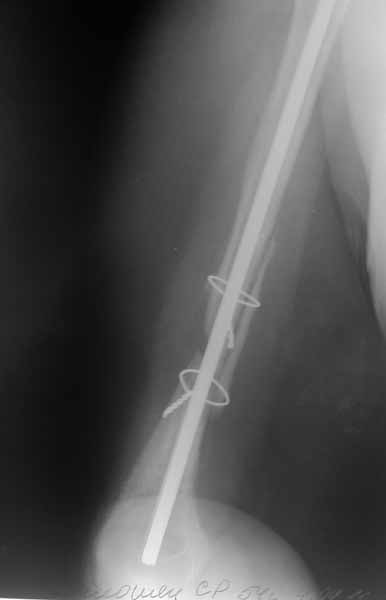

Доброго времени суток уважаемые коллеги.Представляю вашему вниманию пациентку 54 лет.Из анамнеза: травма в сентябре 2010 года в результате падения. В ЦРБ по м/ж выполнена открытая репозиция, синтез штифтом Кюнчера и проволочным серкляжами.

Рана заживала первично.Такая исходная длина штифта разъяснена пациентке как "непринципиальный" момент в общем процессе лечения. Гипсовая иммобилизация 2 месяца. По снятию гипсовой повязки пациентка отметила резкое снижение объема движений в плечевом суставе. Активное длительное ЛФК без эффекта.